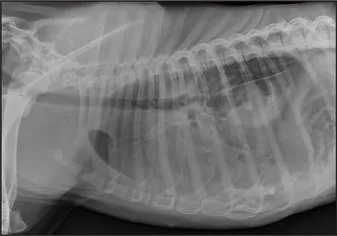

CASE 1.1 A 7-year-old neutered male Labrador Retriever who was hit by a car. You obtain these thoracic radiographs: Figs. 1.1a, b, left and right lateral projections, respectively; Figs. 1.1c, d, ventrodorsal and dorsoventral projections, respectively.

1.1b